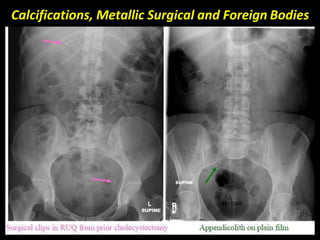

Calcifications, Metallic Surgical and Foreign Bodies

AP ABDOMEN

(MALE).

FEMALE.